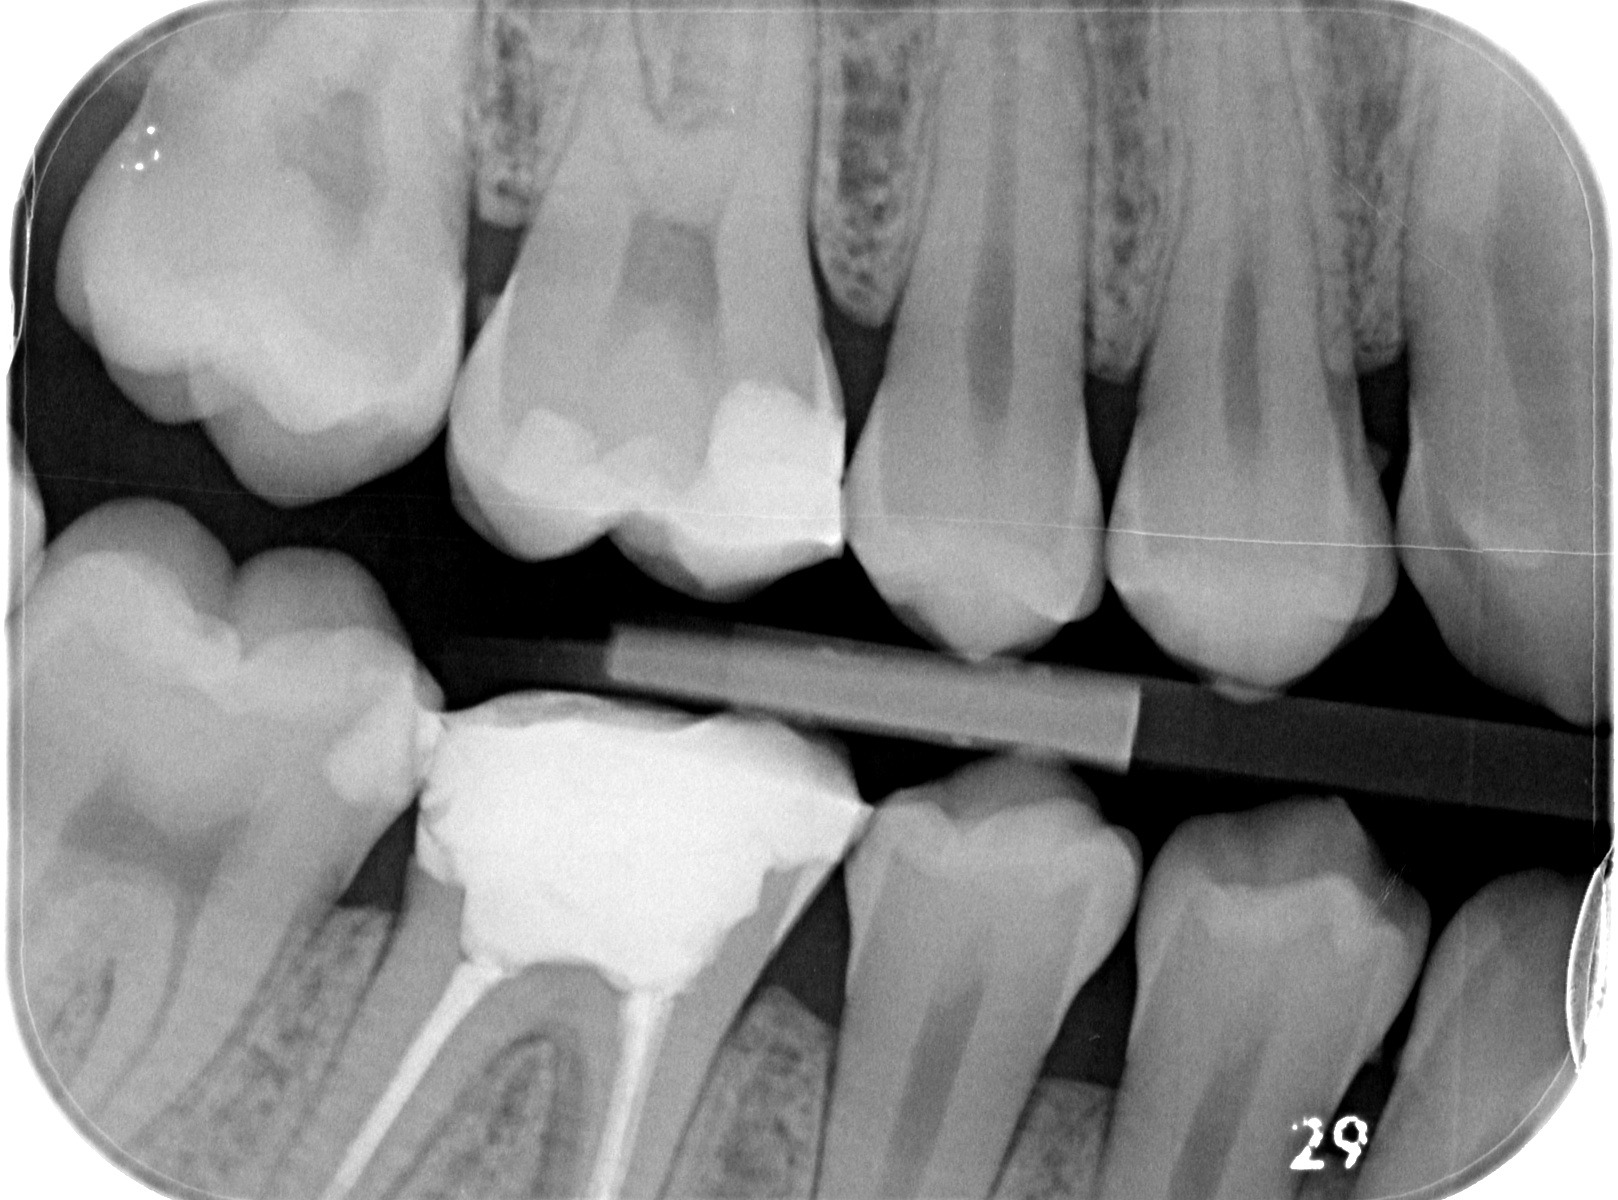

Ich hatte im März diesen Jahres eine starke Pulpitis mit submukösem Abszess des Zahnes regio 46. Es wurde eine Inzision zur Abszessentlastung durchgeführt, eine Drainage in Form einer Lasche eingelegt und eine Wurzelbehandlung durchgeführt, welche sich ca. über 4-5 Sitzungen streckte, bis der Zahn sich letztlich beruhigte und im Juni verschlossen wurde. Seitdem habe ich auch keine Schmerzen mehr beim kauen, kein pochen, pulsieren oder ähnliches. Jedoch habe ich gemerkt dass sich der Zahn bei Druck links und rechts an den Zahnwänden minimal im Zahnfach bewegen lässt, was auch spürbar ist. Mit bloßem Auge kaum sichtbar, nur bei genauerem hinsehen. Beim abklopfen der Zahnwände links und rechts verspüre ich einen leichten Schmerz. Ist das eine Indikation für eine fehlgeschlagene WB oder gibt es dafür eine andere Erklärung? Auf der Bissflügelaufnahme scheinen die Zahnwände nämlich schon recht dünn und die Füllung ziemlich groß. Hat das etwas damit zu tun? Was mir auch aufgefallen ist, ist das im Vergleich des Zahnes regio 36 die Füllung etwas niedriger ist.

P.S. Die mit blauen Pfeilen markierten Zähne im Panoramaröntgen wurden schon behandelt. Das Röntgen wurde am 28. Oktober dieses Jahr gemacht. Ebenfalls habe ich Ihnen einen Vergleich des Zahns regio 46 und 36 angehängt, damit Sie eventuell sagen können, ob die Füllung zu niedrig ist.